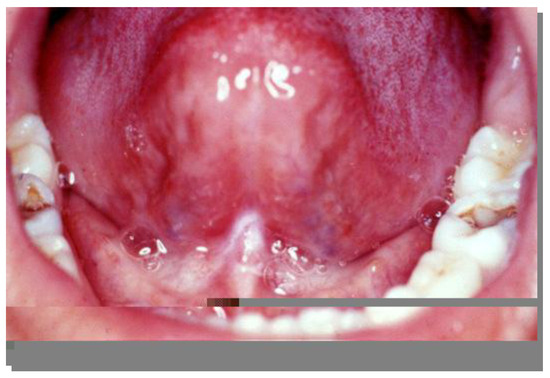

Figure 4.

Lingual frenum before surgery. Note the difficulty during tongue elevation.

Preoperative aspect of patient undergoing speech therapy for 1 year.

Figure 8.